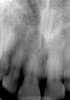

Figure 7A Deep caries evident on the radiograph for tooth No. 9.

Figure 7A

Figure 7B Pulp vitality testing for tooth No. 9 using Gentle-Pulse Pulp Vitality Tester

Figure 7B